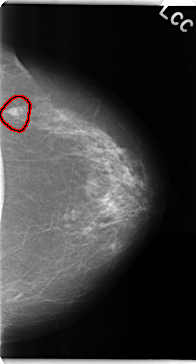

C_0135_1.LEFT_CC

FILE: C_0135_1.LEFT_CC.OVERLAY

TOTAL_ABNORMALITIES 1

ABNORMALITY 1

LESION_TYPE MASS SHAPE OVAL MARGINS MICROLOBULATED

ASSESSMENT 4

SUBTLETY 5

PATHOLOGY MALIGNANT

TOTAL_OUTLINES 1

BOUNDARY